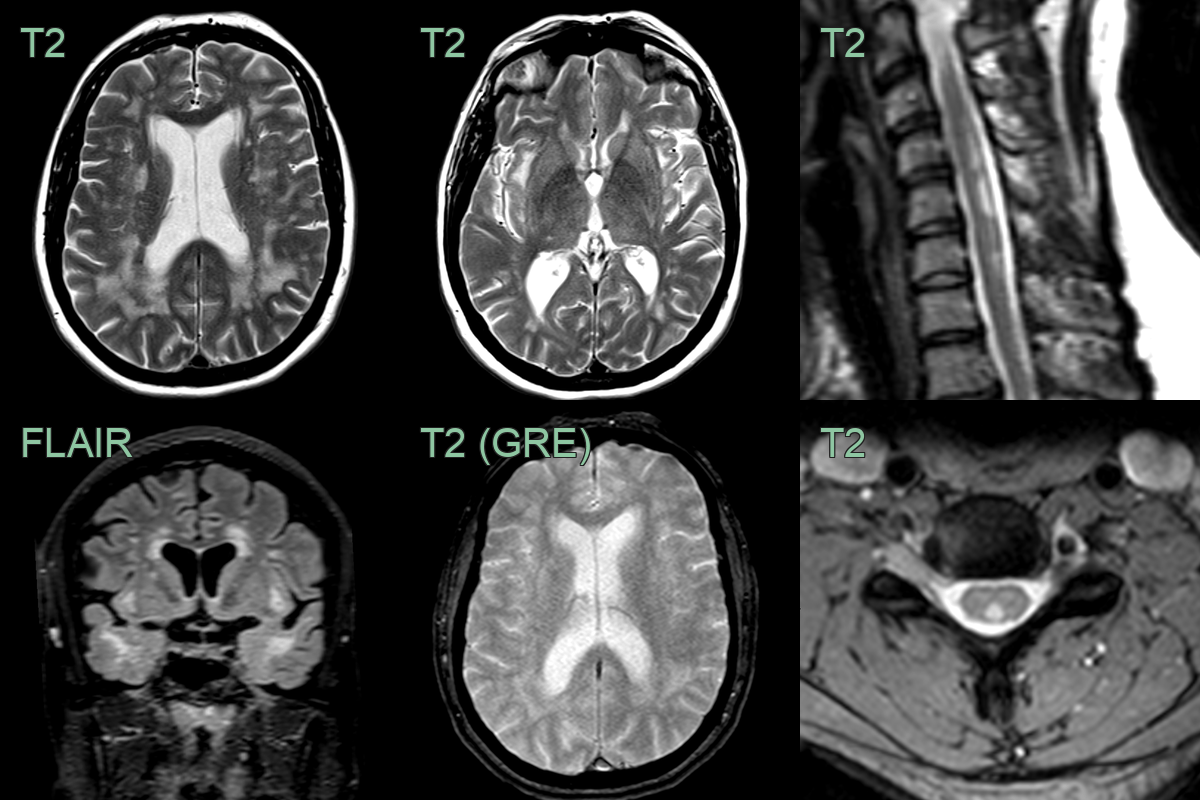

• Alongside the classical intracranial features of CADASIL, MRI showed multiple dorsal column hyperintensities.

• With no evidence of a metabolic or demyelinating cause, findings were ascribed to a CADASIL-related myelopathy.